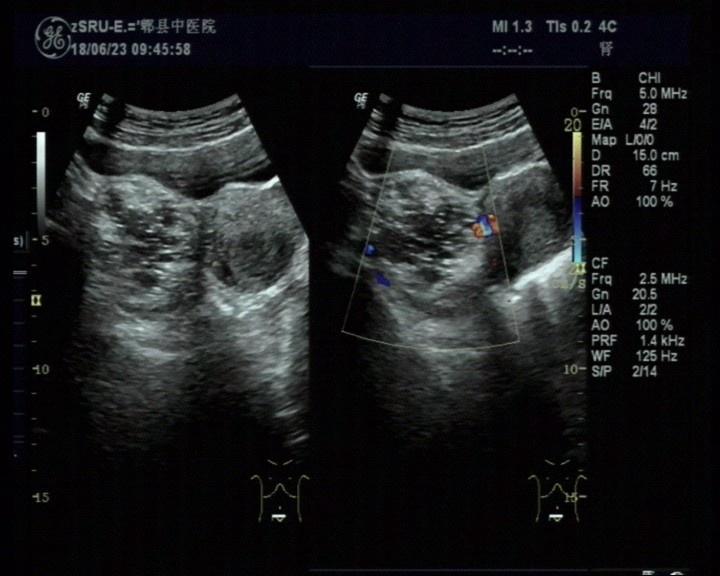

右侧附件区畸胎瘤可能

女,30岁,既往体检无异常,此次超声检查如图所示:右侧附件区探及一杂乱不均回声团,边界清楚,形态规则,CDFI:周边可见少许血流信号。

这样子一坨 除了考虑畸胎瘤 也好像没有别的选项了啊还有一种囊腺瘤